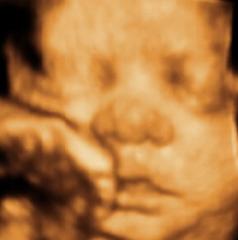

3d Ultrasound Orange County Ny

3d 4d Ultrasounds Baby S Debut Albany New York

3d Imaging Services

3d 4d Hd Ultrasound 3d Maternity Imaging Gender Reveal New

Middletown

Baby S Bungalow Lets You See The Love Of Your Life Like No One